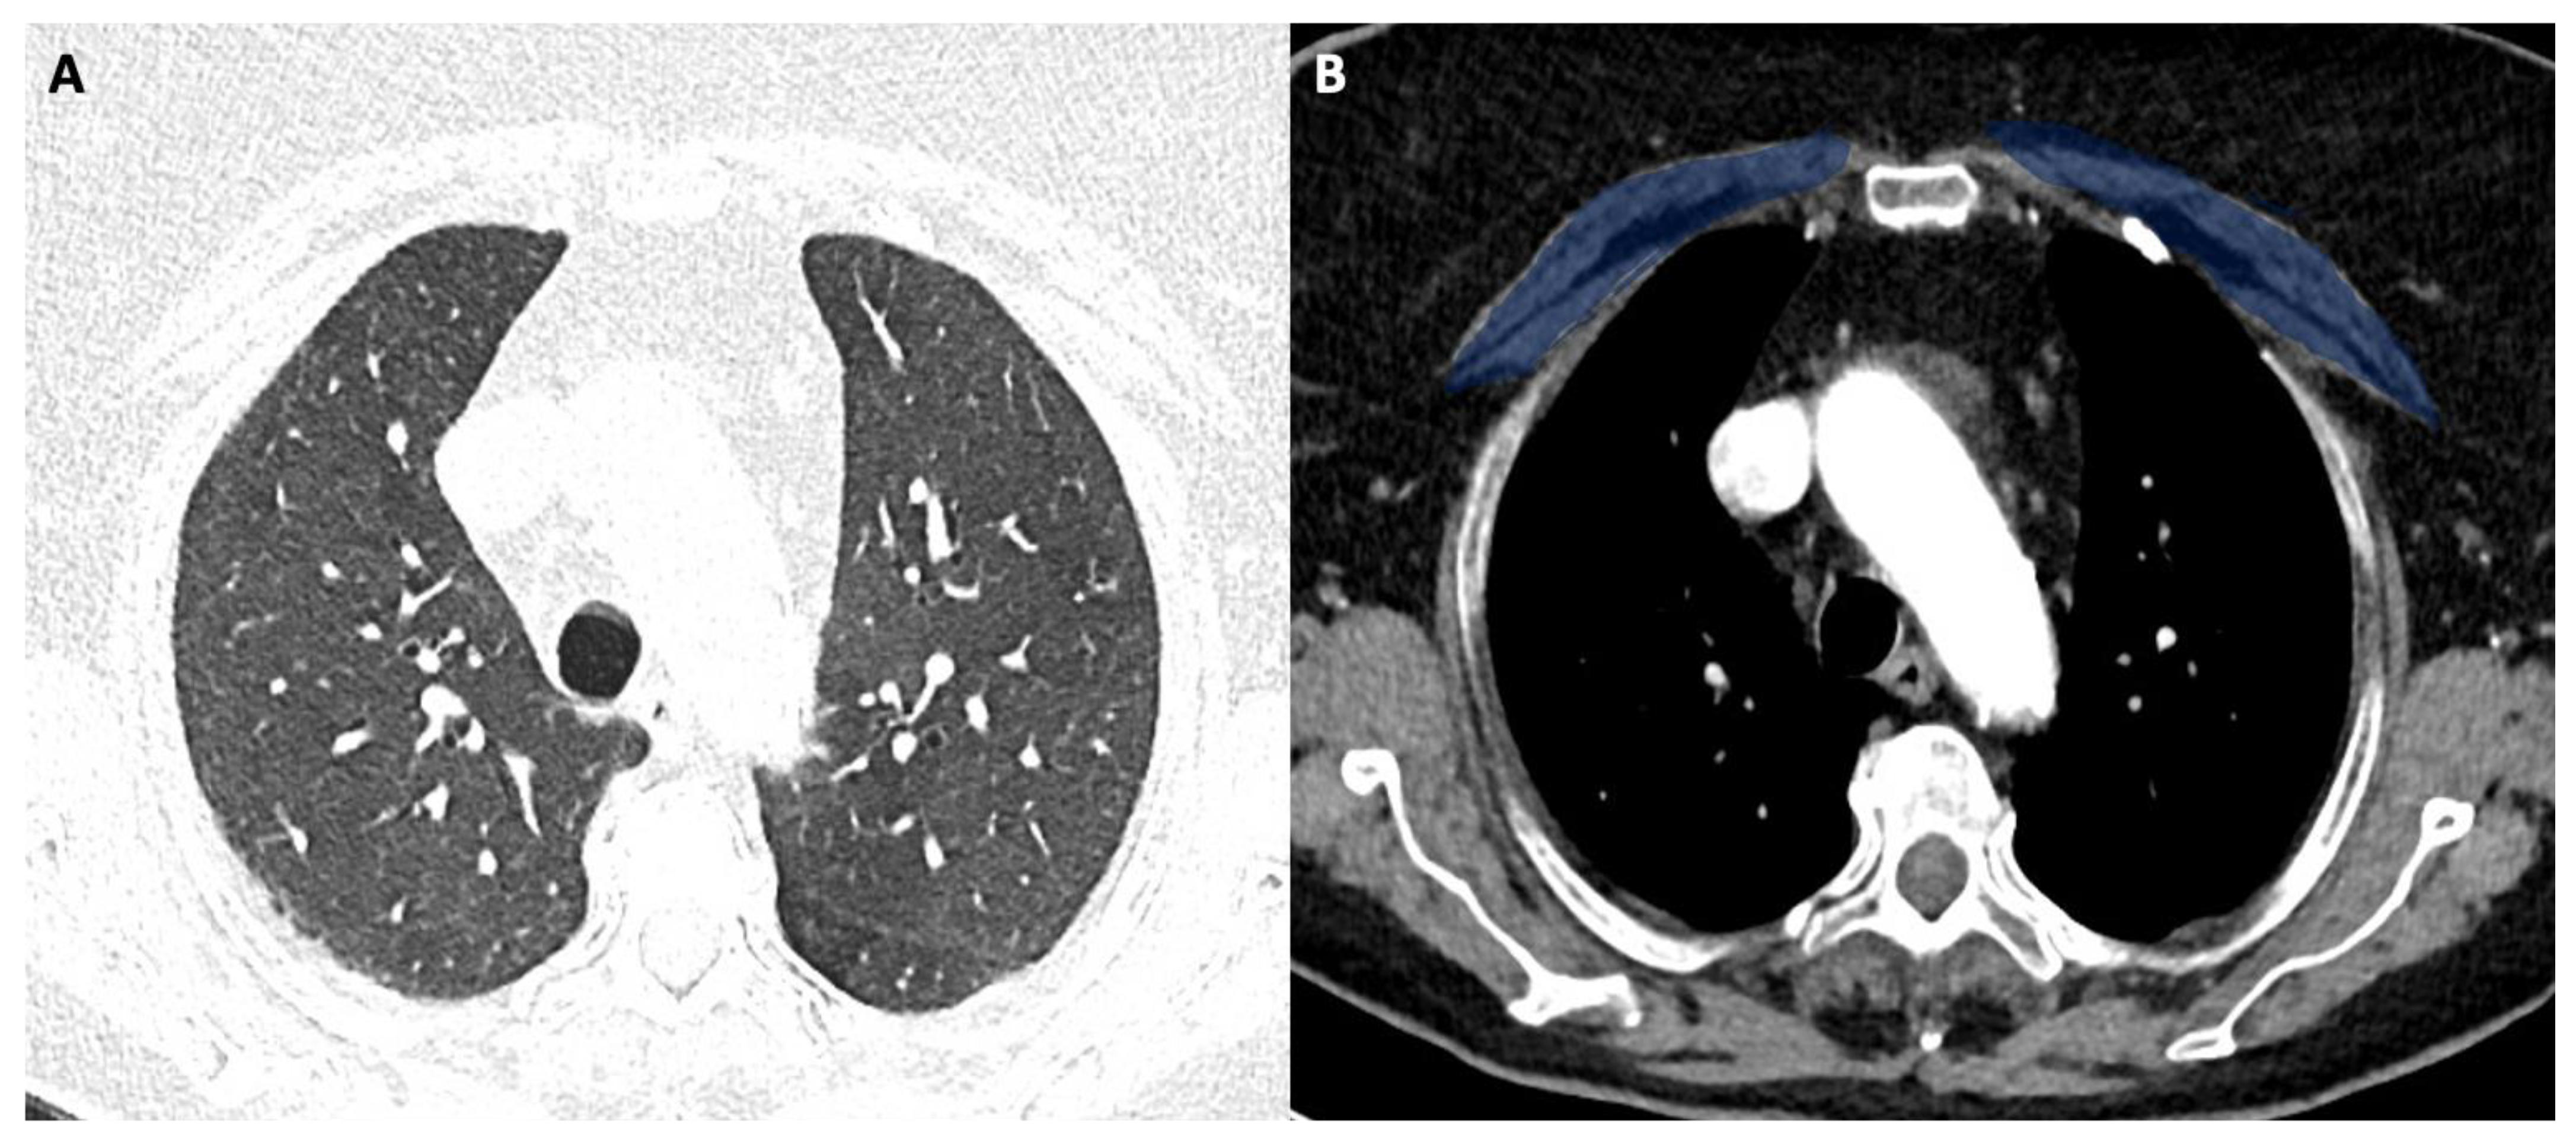

Figure 2A shows the CT image with lung window (pneumonia severity index score: 5). Figure 2B shows the corresponding level in the mediastinal window with high pectoral muscle area (blue area). The patient had a long ICU stay, and he had successful extubation.

Figure 3A shows the CT image with lung window (pneumonia severity index score: 8). Figure 3B shows the corresponding level in the mediastinal window with a low pectoral muscle area (blue area). The patient had a long ICU stay, and he had extubation failure.